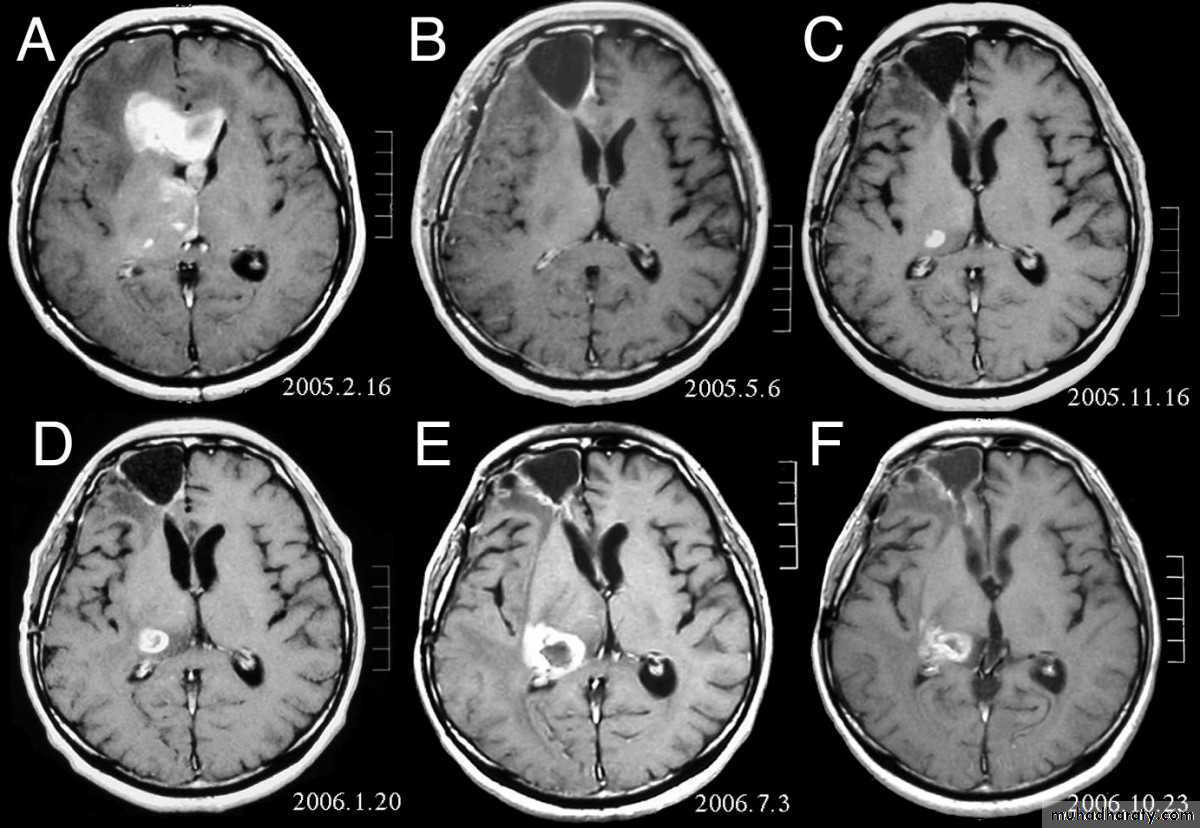

ANAPLASTIC ASTROCYTOMA AXIAL MRI’S

GLIOBLASTOMA MULTIFORMI

GM AXIAL MRI